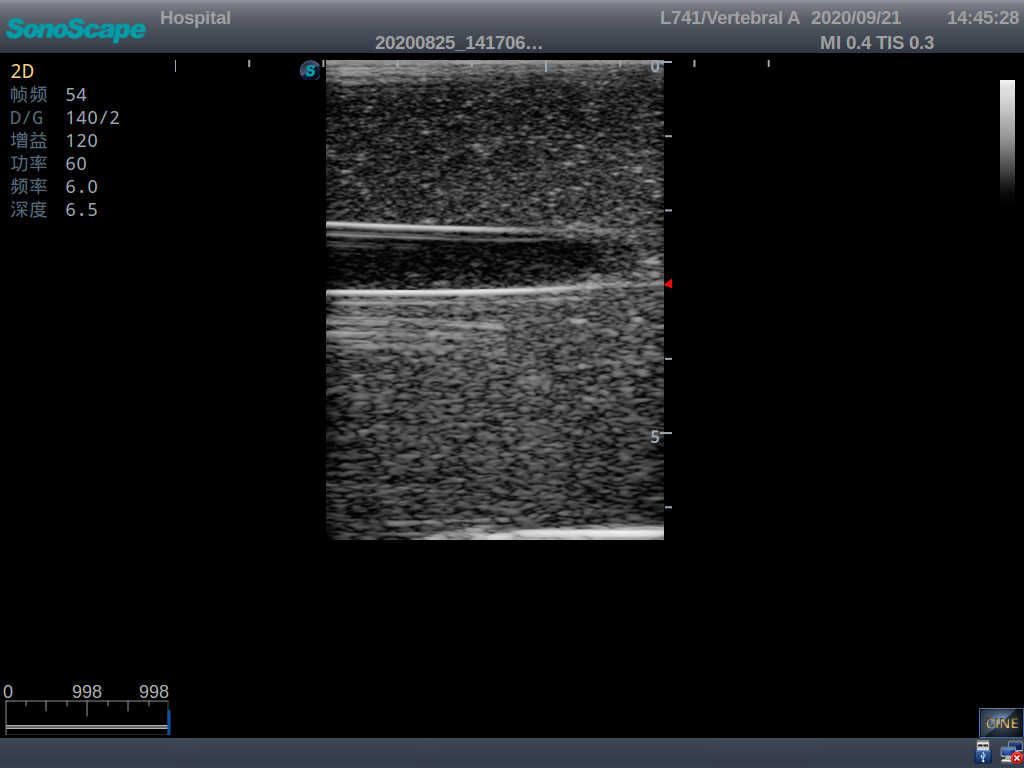

Vascular Access Ultrasound Training Model

Model TYE4034

Product size(mm) 170×130×65

The model is designed for simulating skin and arteriovenous puncture. It contains an artery and a vena comitans. Trainees can practice arteriovenous identification, arteriopuncture and venipuncture.

1) Made of high molecular polymer ultrasound material, close to real skin. It can conduct ultrasound-guided puncture exercises with various clinical models of real ultrasound machines

2) Clear and real images of arteries and veins

3) Showing physiological phenomena that veins are easier to be flatted than arteries under external pressure

4) When conducting vascular puncture, the piercing can be truly felt

5) Externally connected with the arterial pulsation ball, which can simulate the arterial pulsation as needed and make the puncture environment more realistic

6) The simulated arteries and veins are respectively externally connected with water bags, ensuring the liquid can be continuously extracted